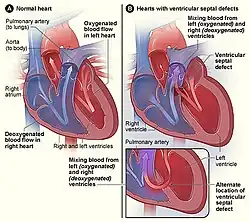

Figure A shows the structure and blood flow in the interior of a normal heart. Figure B shows two common locations for a ventricular septal defect. The defect allows oxygen-rich blood from the left ventricle to mix with oxygen-poor blood in the right ventricle.

Figure A shows the structure and blood flow in the interior of a normal heart. Figure B shows two common locations for a ventricular septal defect. The defect allows oxygen-rich blood from the left ventricle to mix with oxygen-poor blood in the right ventricle.

A ventricular septal defect arises when the superior part of the interventricular septum, which separates the right and left ventricles of the heart, fails to fully develop. The right ventricle pumps blood to the lungs to get oxygen, while the left ventricle pumps blood to the rest of the body to provide oxygen to tissues. A ventricular septal defect results in the mixing of oxygen-rich blood with oxygen-poor blood, increasing strain on the heart and lungs.[11]

During ventricular contraction, or systole, some of the blood from the left ventricle leaks into the right ventricle, passes through the lungs and re-enters the left ventricle via the pulmonary veins and left atrium. This has two net effects. First, the circuitous refluxing of blood causes volume overload on the left ventricle. Second, because the left ventricle normally has a much higher systolic pressure (~120 mmHg) than the right ventricle (~20 mmHg), the leakage of blood into the right ventricle therefore elevates right ventricular pressure and volume, causing pulmonary hypertension with its associated symptoms.

In serious cases, the pulmonary arterial pressure can reach levels that equal the systemic pressure. This reverses the left to right shunt, so that blood then flows from the right ventricle into the left ventricle, resulting in cyanosis, as blood is by-passing the lungs for oxygenation.[12]